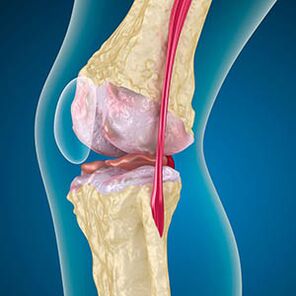

Artroosiga on luude servade vooderdav kõhre hõõrdumine või täielikult puudumine. Kahjustatud kude ei ole valu allikas, kuna sellel pole retseptoreid. Põletik läheduses asuvates struktuurides põhjustab iseloomulikke sümptomeid.

Keha jätkab kahjustatud kudede taastumist, kuid kõhre kasvab ebaühtlaselt. Selle tulemusel moodustuvad ebakorrapärasused, mis vigastavad liigese muid elemente. Osteofüütide olemust seletatakse sujuva liigese kõhre kompensatsiooniga. Teine versioon näitab, et "Spursi" kasv See on seotud katsega stabiliseerida liigest mediaalselt või külgsuunas lihaste nõrgenemise tõttu.

Radiograafia näitab osteofüütide olemasolu, reie- ja sääreluu luude vahelise ruumi muutust, mis näitab kõhre kadu põlvedes. Mõnikord ilmneb põlveliigeste X -ray kõhre kulumise olulised tunnused, kuid patsientidel ei teki olulist valu.Vastupidi, esimese etapi artroos võib häirida põlve funktsiooni, kuna valu põhjustajaks on hüpotoonilised lihased.